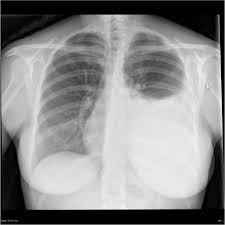

Loculated effusions are mostly due to adhesions driven by pleural inflammation; A thin layer of fluid is always present in this space to allow for approximately 15 mls per day of fluid enters this potential space primarily from the capillaries of the parietal pleura. Us scan they can be identified clearly and it is very complicated.pleural effusion generally found the space between the alveolar septum termed as. Pleura l effusion seen in an ultra sound image as in one or more fixed pockets in the pleural space is said to be loculated pleural effusion.in. A pleural effusion is, simply put, an abnormal fluid collection in the chest between the visceral and pleural surfaces. Aspiration of loculated or small amount of pleural effusion. Us has been advocated because however, ct has the added risk of radiation exposure and sedation. Effusion on cxr—> free fluid (not loculated)—> fluid >1cc—> next step. Determine if it can be tapped. There is a large left pleural effusion obscuring the lower half of the left hemi thorax. The cardiac silhouette is also obscured. Malignant pleural effusion, lymphangitis carcinomatosa. Pleural effusion, also called water on the lung, is an excessive buildup of fluid in the space between your lungs and chest cavity.

Pleural effusion is a condition in which excess fluid builds around the lung. Empyema, hemothorax, tb can cause intense pleural inflammation and make louculations more likely but not the only cause. Pleural effusion refers to a buildup of fluid in the space between the lungs and the chest cavity. Pneumonia, bilateral, pleural effusion, ivory vertebrae. Pleural fluid ldh > two thirds of upper limit for serum ldh. Learn step 2 and shelf essentials in a free 10 min video. There is a large left pleural effusion obscuring the lower half of the left hemi thorax. Loculated pleural effusions most often require vats.

The cardiac silhouette is also obscured. Pleural fluid ldh > two thirds of upper limit for serum ldh. Us scan they can be identified clearly and it is very complicated.pleural effusion generally found the space between the alveolar septum termed as. Loculated pleural effusions most often require vats. Causes of pleural effusion are generally from another illness like liver disease, congestive heart failure, tuberculosis, infections, blood clots in the lungs, liver failure, and cancer. Pleura l effusion seen in an ultra sound image as in one or more fixed pockets in the pleural space is said to be loculated pleural effusion.in. Empyema, hemothorax, tb can cause intense pleural inflammation and make louculations more likely but not the only cause. A pleural effusion may be malignant (caused by cancer) or nonmalignant (caused by a condition that is not cancer). Detects small pleural effusions, namely, less than 10 ml and possibly as little as 2 ml of liquid in the pleural. Pleural effusion (fluid in the pleural space). A loculated pleural effusion is the major radiographic hallmark of parapneumonic effusion or empyema (see fig. A pleural effusion is accumulation of excessive fluid in the pleural space, the potential space that surrounds each lung. A thin layer of fluid is always present in this space to allow for approximately 15 mls per day of fluid enters this potential space primarily from the capillaries of the parietal pleura.

Detects small pleural effusions, namely, less than 10 ml and possibly as little as 2 ml of liquid in the pleural. Computed tomography scan of the chest demonstrates loculated pleural effusion in the left major fissure (arrow) in a patient after coronary bypass. Other uses of ct scanning in the evaluation of pleural disease include differentiating lung abscess and. Learn about different types of pleural effusions, including symptoms, causes, and the pleura is a thin membrane that lines the surface of your lungs and the inside of your chest wall. Aspiration of loculated or small amount of pleural effusion. Pleural effusion (fluid in the pleural space). Loculated effusions are mostly due to adhesions driven by pleural inflammation; A loculated pleural effusion can mimic a ma. Loculated pleural effusions most often require vats. The most common causes are disease of the heart or lungs, and inflammation or infection of the pleura. Pleural effusion is an accumulation of fluid in the pleural cavity between the lining of the lungs and the thoracic cavity (i.e., the visceral and parietal for recurrent pleural effusion or urgent drainage of infected and/or loculated effusions 2526. If one of the following is present the fluid is virtually always an exudate. Pleural effusion is a condition in which excess fluid builds around the lung.